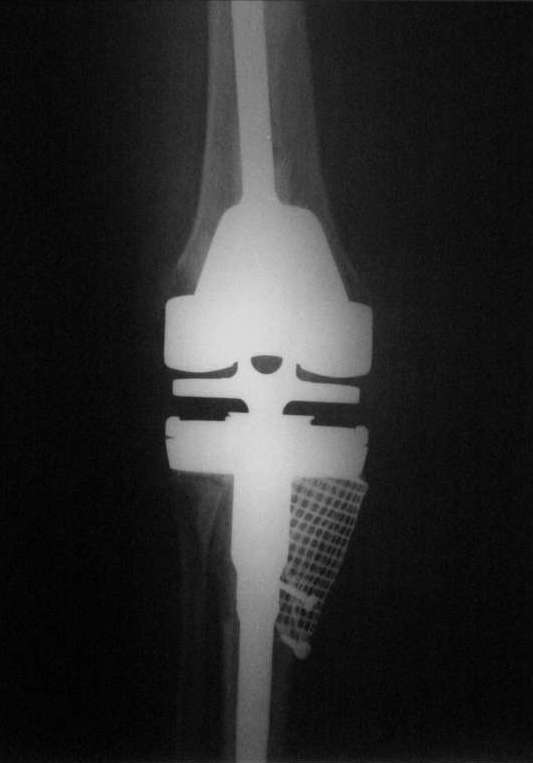

Вот то, что получилось и снимки во время операции.С уважением, Римашевский Д.

Рассверлили канал большеберцовой кости. В канал поставили стержень. По нему, на наружный кортикал посадили шаблон тибиального компонента (см. фото). Определили размер дефекта внутреннего мыщелка, который надо закрыть сеткой.

На внутренний мышелок установили сетку из нержавеющей стали Ex-Change Stryker (предназначенную для укрепления верхнего края вертлужной впадины) и фиксировали её 4 винтами. Подрезали сетку сверху по шаблону тибиального компонента. После этого рассверлили канал б/б и бедренной костей под протез. Используя систему пульс-лаважа Stryker SurgiLav c насадкой - щеткой для промывания каналов промыли бедренную и большеберцовую кости. Последнее сверло, которым рассверливали проксимальную часть канала б/б кости, оставили на месте. Аллотрансплантат перемололи на костной мельнице, перемешали с 3 гр. ванкомицина и достаточно плотно заполнили им дефект внутреннего мыщелка, утрамбовывая импактором костную стружку в единую массу.

Так как наружный кортикал был на 1.3 см. ниже головки малоберцовой кости, пришлось использовать вставку под большеберцовый компонент 1 см. На цемент c ванкомицином поставили тибиальный компонент с ножкой 11/80 мм.

Бедро по шаблону резецировали (лучше сказать «причесали»). Системой пульс-лаваж с щеткой для отмывания костной поверхности основательно все отмыли и поставили на цемент бедренный компонент c ножкой 11/155 мм.